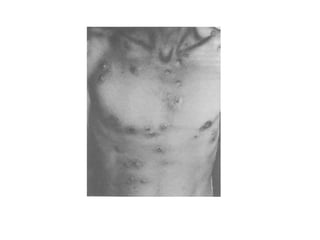

Sífilis maligna

• Esta rara manifestação clínica constitui

variante da sífilis secundária.

• Caracteriza-se por lesões ulceradas

pustulosas, extensas e às vezes de

caráter rupióide.

• Em revisão de 31 casos de sífilis maligna,

Haslund demonstrou que geralmente

existe um pródromo de febre, cefaléia e

mialgia antes do aparecimento das lesões

cutâneas.

• As lesões cutâneas geralmente se iniciam

como pápulo-pústulas que rapidamente se

tornam necróticas.

• A face e couro cabeludo são as áreas

mais freqüentemente envolvidas, seguidos

dos membros e tronco.

Neisser ressalta quatro características

clínicas da sífilis maligna precoce:

• a. A doença apresenta período de incubação relativamente curto -

Haslund define o período de incubação mínimo de quatro a seis

semanas e o máximo de um ano;

• b. Sintomas sistêmicos pronunciados;

• c. A pele e freqüentemente a mucosa nasal e bucal apresentam

lesões irregularmente distribuídas, constituídas por pústulas,

úlceras e lesões rupióides;

• d. As lesões cutâneas são pleomórficas e revelam pápulo-pústulas,

ulcerações profundas, às vezes recobertas por crostas e lesões

cicatriciais. A pele ao redor das lesões é pouco afetada,

apresentando mínimo eritema.